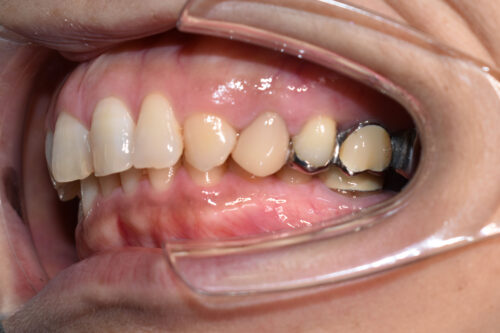

初診時年齢 46歳 女性

歯のでこぼこ(叢生)

左側完全クロスバイトの治療を

左側の小臼歯部から

大臼歯部にかけて

クロスバイトを呈し

過蓋咬合の状態でした。

ワイヤー矯正治療1年2か月後です。